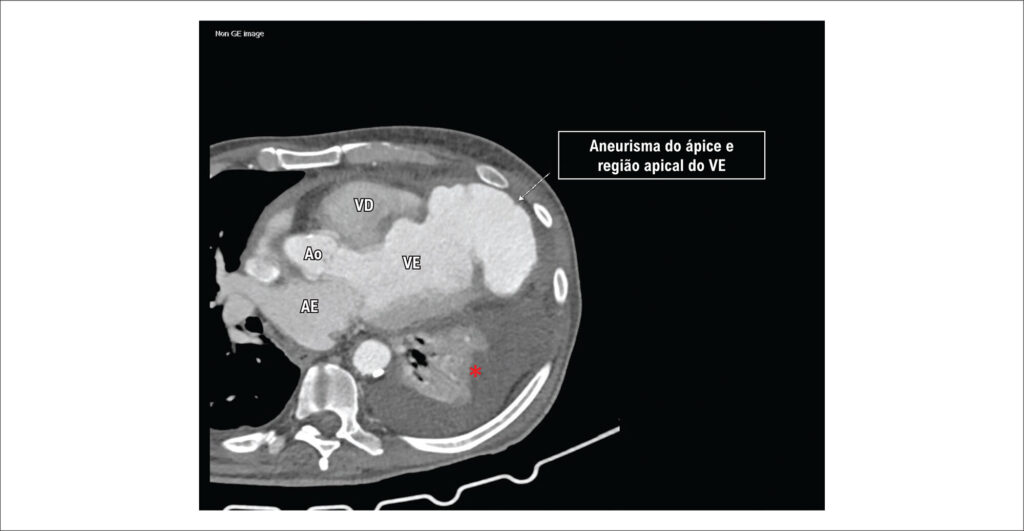

Aneurisma de Ventrículo Esquerdo Roto e Contido: Um Relato de Caso

AVE ocorrem meses ou anos após o infarto agudo do miocárdio. São formados por área de tecido cicatricial e contêm as três camadas da parede ventricular (endocárdio, miocárdio e pericárdio), sendo sua parede íntegra, podendo conter trombos. Já o PAVE é uma complicação rara que pode ocorrer dias ou meses após o infarto, sendo formado pela parede enfraquecida que se rompe após o infarto, de modo que esta ruptura é contida pelo pericárdio, havendo descontinuidade da borda endocárdica. Usualmente, AVE são localizados nas regiões apical e anterior, enquanto PAVE se localizam na região póstero-lateral do ventrículo esquerdo.